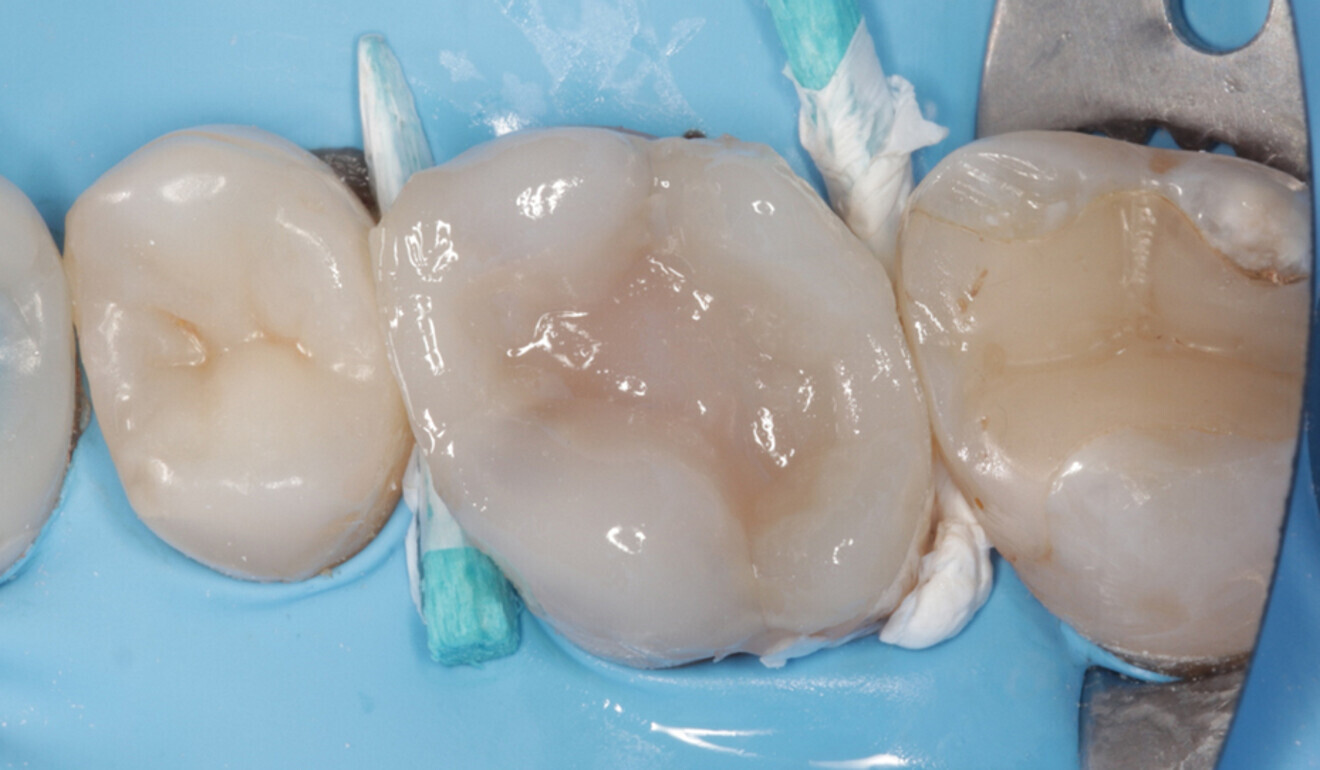

The initial polishing was performed with the dental dam still in place. The excess composite resin was removed with the aid of abrasive discs, diamond burs and a Brownie polisher (BAL, Nevadent). Pre-polishing and high-shine polishing were executed with TWIST DIA for Composite (Kuraray Europe) supported by a goat hair brush (Micerium; Figs. 16 & 17).

Fig. 16: Occlusal surface after surface modelling with CLEARFIL MAJESTY ES-2 Universal and initial polishing, occlusal view. (Image: Kuraray Noritake Dental)